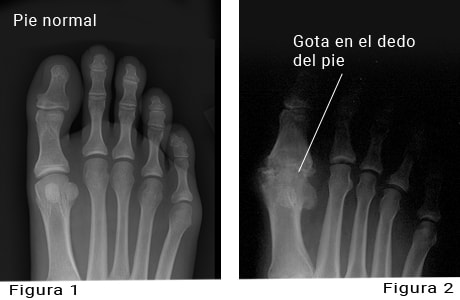

Gota